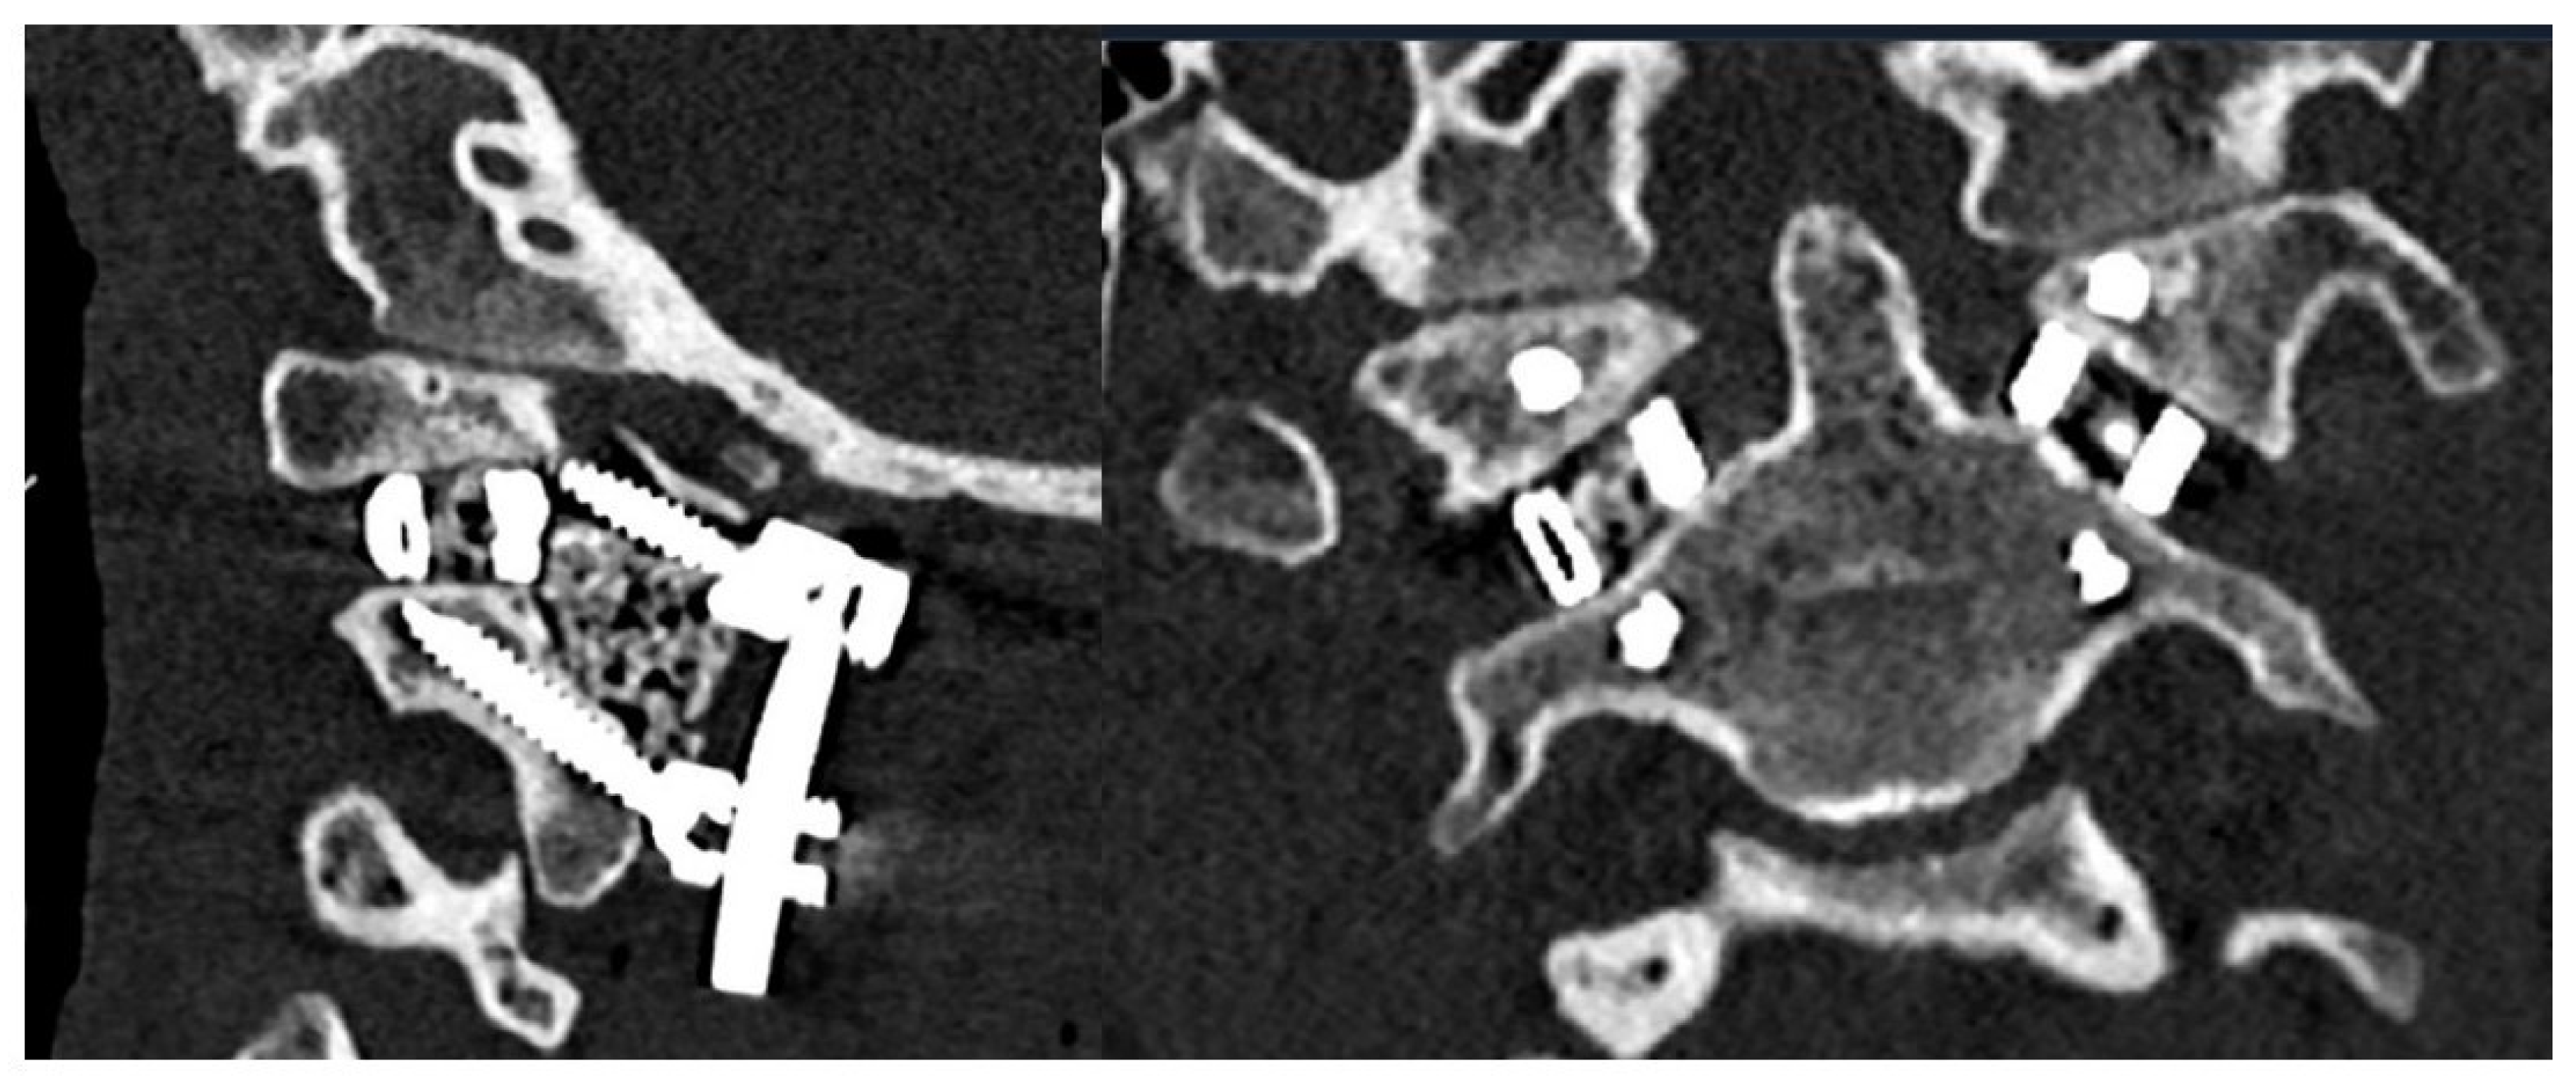

4. Results